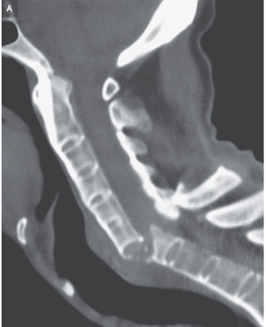

頚部CT施行。C6~C7レベルで位置がずれた骨折(「チョーク骨折」とも呼ばれる)を伴う癒合した椎骨を認めた。